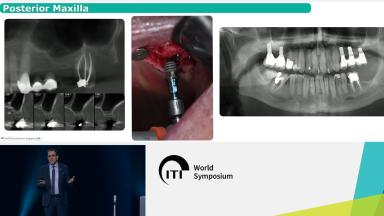

ITI World Symposium 2024 lecture by Waldemar Polido - part of the "GBR/Bone Augmentation" session.

Several surgical techniques can be employed to vertically reconstruct atrophic alveolar bone.However, these ancillary techniques have higher morbidity and are technique sensitive, potentially leading to more complications in the hands of less experienced surgeons. The use of short implants is an alternative to adequately restore partially edentulous patients. Its use has grown exponentially on the last years due to great improvements on imaging, virtual planning, materials and techniques. Recently, ultra-short implants have been introduced, showing promising results for the rehabilitation of patients with severely resorbed alveolar ridges.

- select the most appropriate short implant in alveolar ridges with deficient vertical bone dimension

- decide whether to use a short implant or carry out a bone regenerative intervention to place longer implants